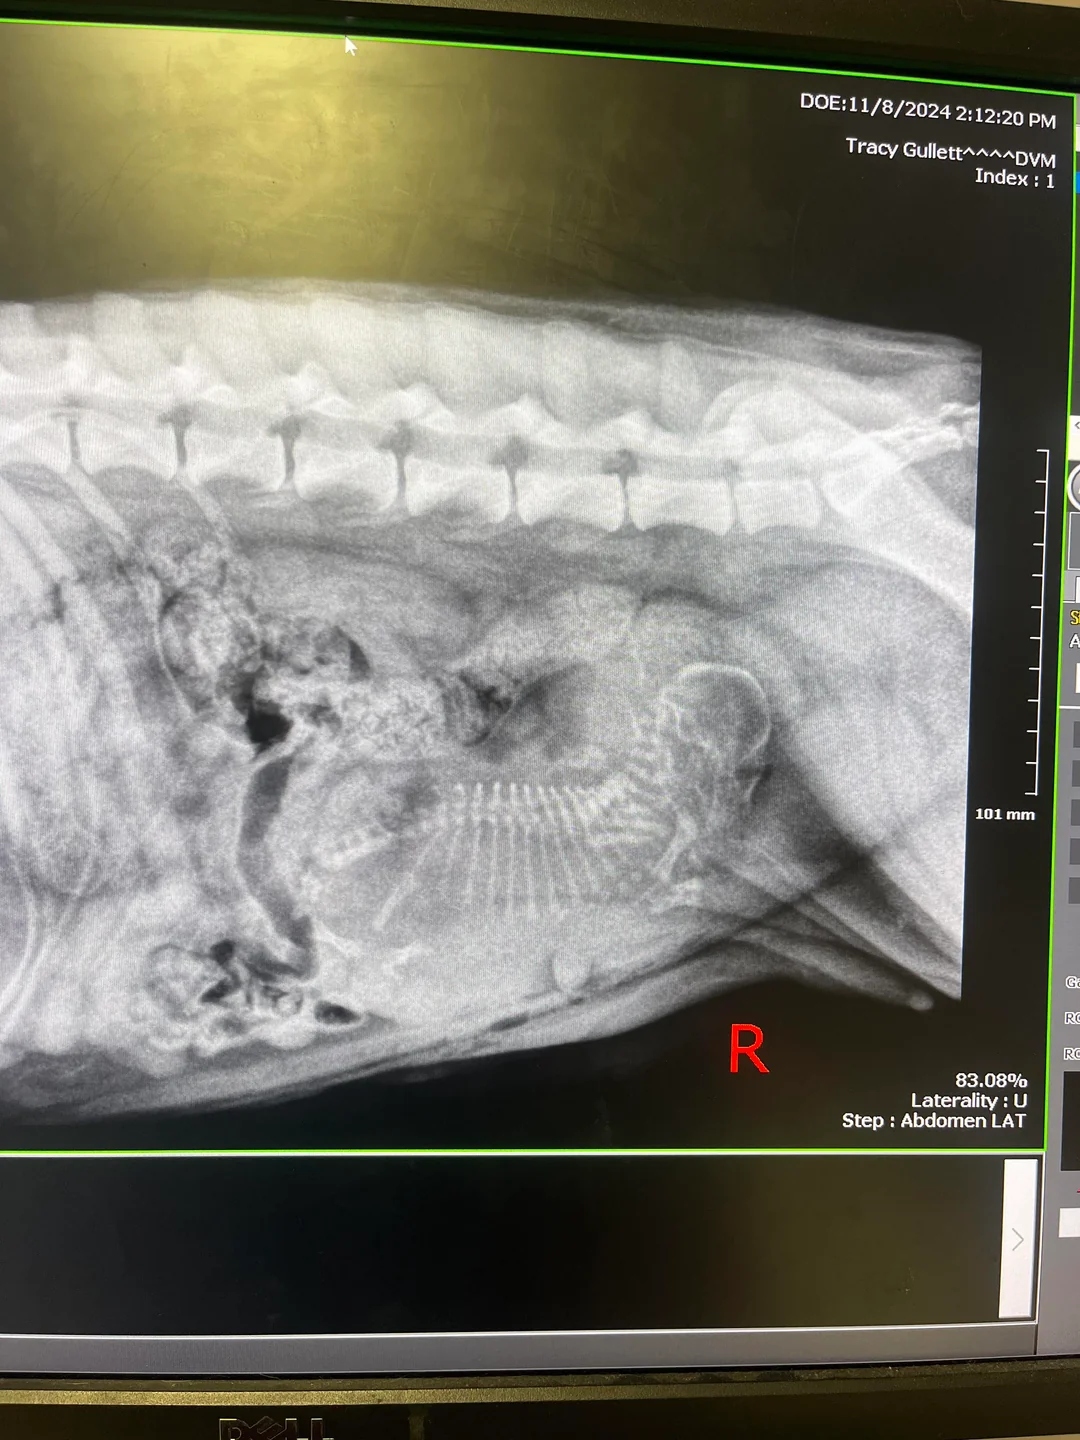

During the surgery, the veterinary staff paused, realizing something completely unexpected. After making the first incision, they discovered that Salem was pregnant.

“Found out at spay appt [appointment] that my new rescue dog is pregnant with one puppy,” Haley wrote in a Reddit post, still shocked by the news.

Her vet explained the situation and discussed the risks with her. Since Salem was carrying only a single puppy, ending the pregnancy could cause complications. Following the advice she was given, Haley made the choice to allow the pregnancy to continue.